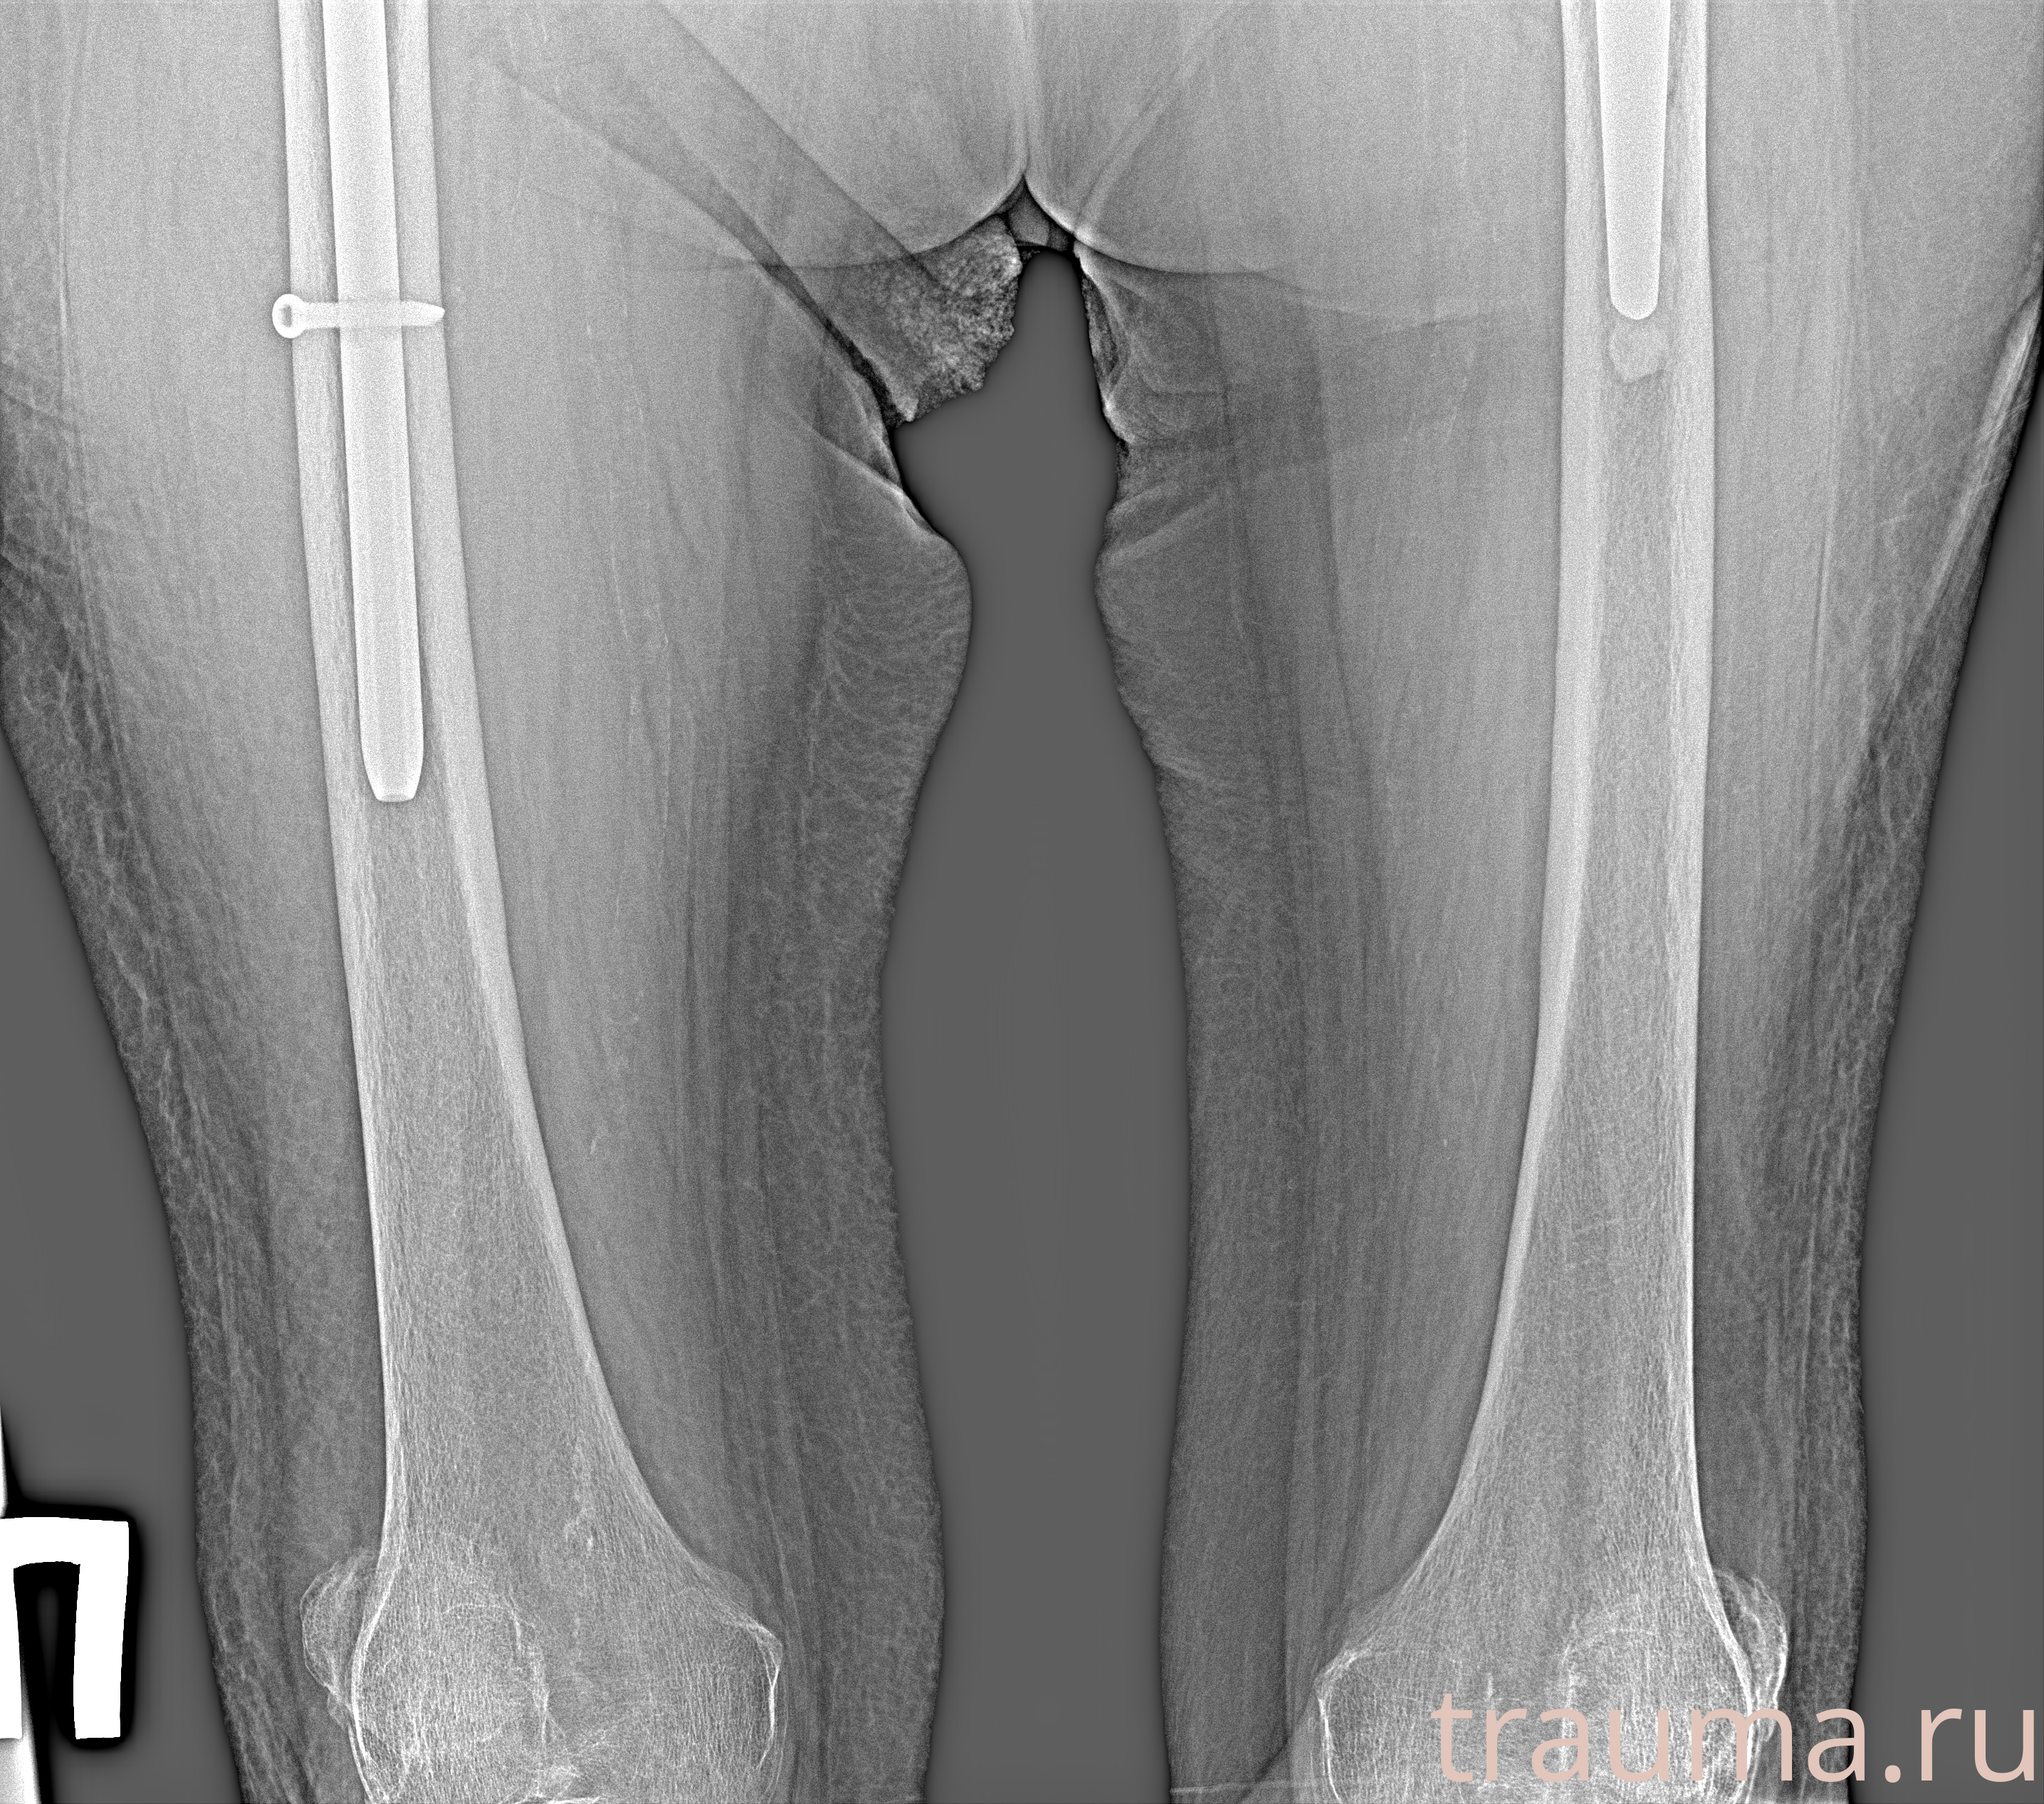

Рентгенограммы

Рентген на дому: по вашему адресу приезжает врач-рентгенолог, травматолог-ортопед с мобильным рентгеновским аппаратом, проводит диагностику травмы или заболевания, делает необходимые рентгенограммы, дает рекомендации по дальнейшему лечению. Получить качественные снимки в домашних условиях возможно благодаря уникальной методике, разработанной МосРентген Центром для института  Склифосовского